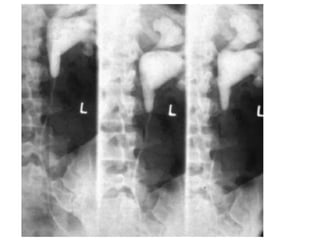

 Straight abdomen of X- ray

 Excretory urography

 Retrograde urography

 Ultrasound